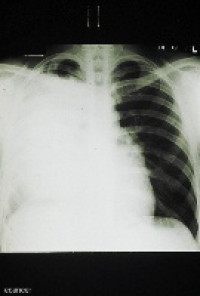

Patients with locally advanced lung cancer, which has spread to only certain lymph nodes, usually undergo surgery to remove their tumours. Unfortunately, the cancer often comes back, so physicians frequently use radiation therapy to decrease patients’ risk of cancer recurrence.

In all, 710 patients (54 percent) received radiation following their surgery, but they were not more likely to survive longer than patients who did not receive radiation. “Our results show that we need more information about the potential benefits of radiation therapy before it is used routinely to treat this subset of lung cancer patients,” said Dr. Wisnivesky.